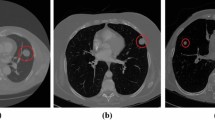

Lung cancer represents one of the most common and lethal types of cancerous pathologies and lung nodules are an early indicator for pulmonary cancer. Hence, a precise and reliable segmentation of lung nodules could enhance early diagnosis and therapy and thus, increase patients’ survival rates. This work proposes a modified 3D-Res2Unet, combining an Unet-style neural network architecture with residual blocks and attention mechanisms. This network was tested on the publicly available LUNA16 CT dataset and achieved on average 91.27 ± 6.49 %. Therefore, the proposed method indicates state-of-the-art performance and could represent an important tool for early diagnosis of lung cancer.

Pezzano G, Ripoll VR, Radeva P. CoLe-CNN: context-learning convolutional neural network with adaptive loss function for lung nodule segmentation. Comput Methods Programs Biomed. 2021;198:105792.

**ao Z, Liu B, Geng L, Zhang F, Liu Y. Segmentation of lung nodules using improved 3D-UNet neural network. Symmetry (Basel). 2020;12(11):1787.

Keetha NV, Annavarapu CSR et al. U-Det: a modified U-Net architecture with bidirectional feature network for lung nodule segmentation. ar**v preprint ar**v:2003.09293. 2020.

Huang X, Sun W, Tseng TLB, Li C, Qian W. Fast and fully-automated detection and segmentation of pulmonary nodules in thoracic CT scans using deep convolutional neural networks. Computerized Medical Imaging and Graphics. 2019;74:25–36.